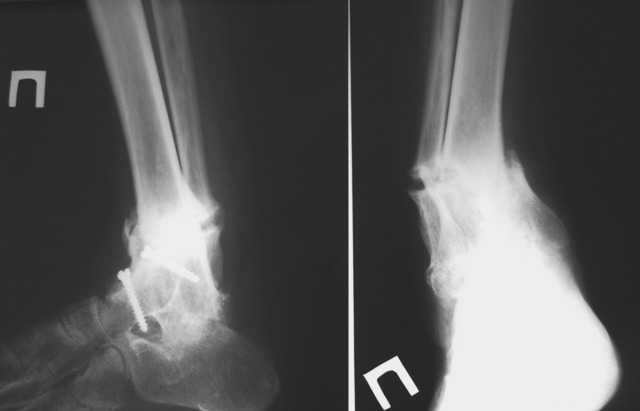

Уважаемые коллеги!Обращаюсь за советом. Пациентка, страдающая ревматоидным артритом, 2 года назад была оперирована по поводу вторичного деформирующего артроза голеностопного сустава с варусной деформацией на этом уровне.

В то время деформация была обусловлена деструкцией тарана, поэтому был выполнен артродез по Кэмпбеллу. Спустя 2 месяца после операции сформировался костный анкилоз голеностопа в физиологическом положении+анкилоз задней фасетки подтарана, пациентка была в восторге, т.к. до этого намаялась со стоптанной обувью, нарушенной походкой, с ортезами и, соответсвенно, с потертостями и гиперкератозами. Тем не менее, нынче обращается с ТЕМИ ЖЕ ПРОБЛЕМАМИ, которые исподволь нарастали в течение 1,5-2 месяцев. Делаем снимки и, о ужас, видим лоозеровскую зону выше анкилоза, клинически тот-же варус. Ясно, что лоозера срастим как-нибудь, но, наверное, надо-бы еще что-то сделать, дабы избежать повторов.PS. С пациенткой доверительные, хорошие отношения.

Женя, сегодня через рассылку пришёл данный случай с *правильными* рентгенограммами. Почему так случилось? Скорее всего (по иному сложно объяснить) деформация с перестройкой кости развилась вследствие не совсем правильной установки стопы в бывшем голеностопном суставе. При артродезировании мы стараемся сместить таранную кость чуть кзади в положении лёгкой функциональной наружной ротации и вальгусом примерно в пять градусов. Отказ от выполнения данных рекомендаций, особенно, в сочетании с избыточным подошвенным сгибением стопы приводит к избыточной нагрузке на средний отдел последней. На фоне ревматоидного артрита и отсутствия должной эластичности среднего и переднего отдела стопы с механической точки зрения возникшая перестройка кости понятна и объяснима.

Что делать? Мне кажется, реально здесь можно сделать выбор или в сторону наружной фиксации с постепенным исправлением деформации с последующей стабилизацией, или в сторону остеосинтеза гвоздём, предназначенным для артодеза голеностопного сустава. Аппарат имеет известные преимущества, связанные с возможностью постепенной и точной коррекции деформации. Недостатки вытекают из этих же преимуществ и общеизвестны так же.

Остеосинтез гвоздём, вводимым через пяточную кость (я бы предпочёл синтезовский HAN, удлинённая версия) позволит добиться того же с меньшими потерями времени и сил для пациенки и врача и предотвратить в определённой степени нечто подобное в будущем. Нужно только проводить рассверливание уже в положении исправленной деформации (временный АВФ может быть полезен), иначе деформация останется.

Согласен с Андреем. Здесь напрашивается дозированное устранение деформации по Илизарову. И по завершении коррекции - закрытое штифтование. Можно сделать его и антеградно большеберцовым стержнем, и ретроградно артродезным.